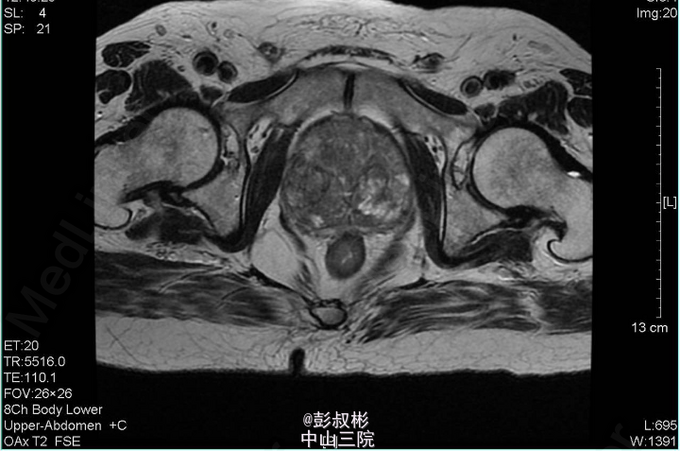

4、查体:直肠指检:前列腺明显增大,大小约:7×6cm,质韧,中央沟消失,可触及一3*2cm结节,质硬,无压痛,界清,指套未见染血 5、辅助检查:外院查尿常规示:红细胞31022个/ul,CA19-9:60.9U/ml,F-PSA:6.45ng/ml,T-PSA:21.2ng/ml,彩超示:膀胱区及前列腺内低回声团,盆腔CT示:膀胱癌并前列腺转移。我院血常规:血红蛋白浓度119.000g/L,白细胞总数7.340x10E9/L。 尿常规:潜血+++,红细胞计数12050.20个/ul,白细胞计数49.50个/ul。 生化全套:肌酐(酶法)218.800umol/L,尿酸658umol/L,血淀粉酶227U/L,谷丙转氨酶64 U/L,谷草转氨酶49U/L,谷氨酰转肽酶340U/L。 PSA两项:总前列腺特异性抗原22.362ng/ml,游离前列腺特异性抗原5.957ng/ml。 盆腔MR:1、考虑前列腺癌并出血,膀胱后壁、双侧精囊腺受压。2、右侧耻骨联合小结节,考虑转移瘤可能性大;左侧坐骨结节所见,未除外转移瘤可能。3、考虑右侧股骨头坏死。胸片示:主动脉硬化,心电图正常。 肺功能:通气功能大至正常。 心脏彩超:EF 65%。主动脉瓣钙化并反流(轻度)。左室收缩功能正常。左室舒张功能减退。 动态心电图:1、窦性心率。2、稀发房早。3、肢体导联低电压 肝胆胰脾彩超:胰头稍大,慢性胆囊炎声像,胆囊多发结石,轻度脂肪肝。 前列腺穿刺:结果未出 骨扫描:全身未见骨转移瘤